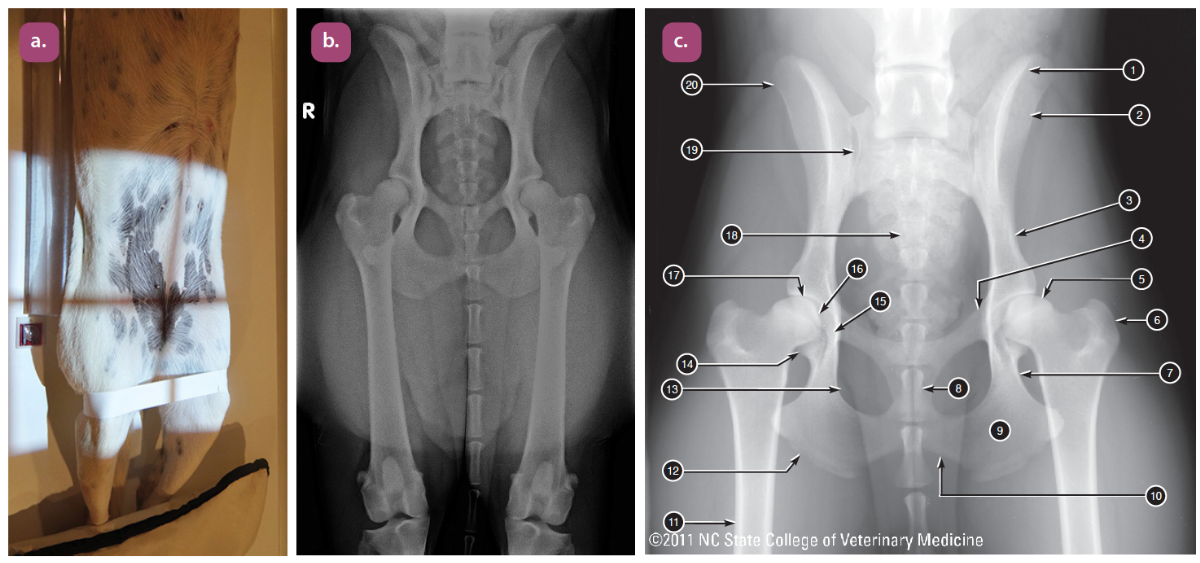

ventrodorsal extended hip projection

ventrodorsal frog leg projection